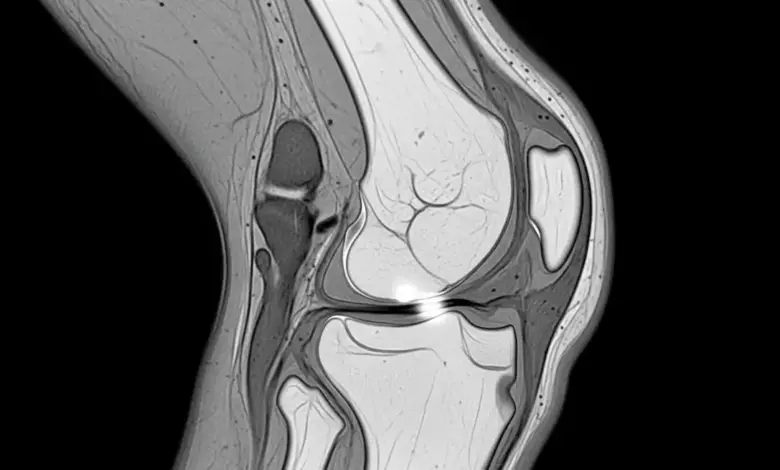

A ressonância magnética pode ajudar, principalmente quando há dúvida diagnóstica ou necessidade de afastar outras lesões associadas.

Ainda assim, o exame precisa ser interpretado junto com a avaliação clínica. Nem toda plica visível no exame é a verdadeira causa da dor.